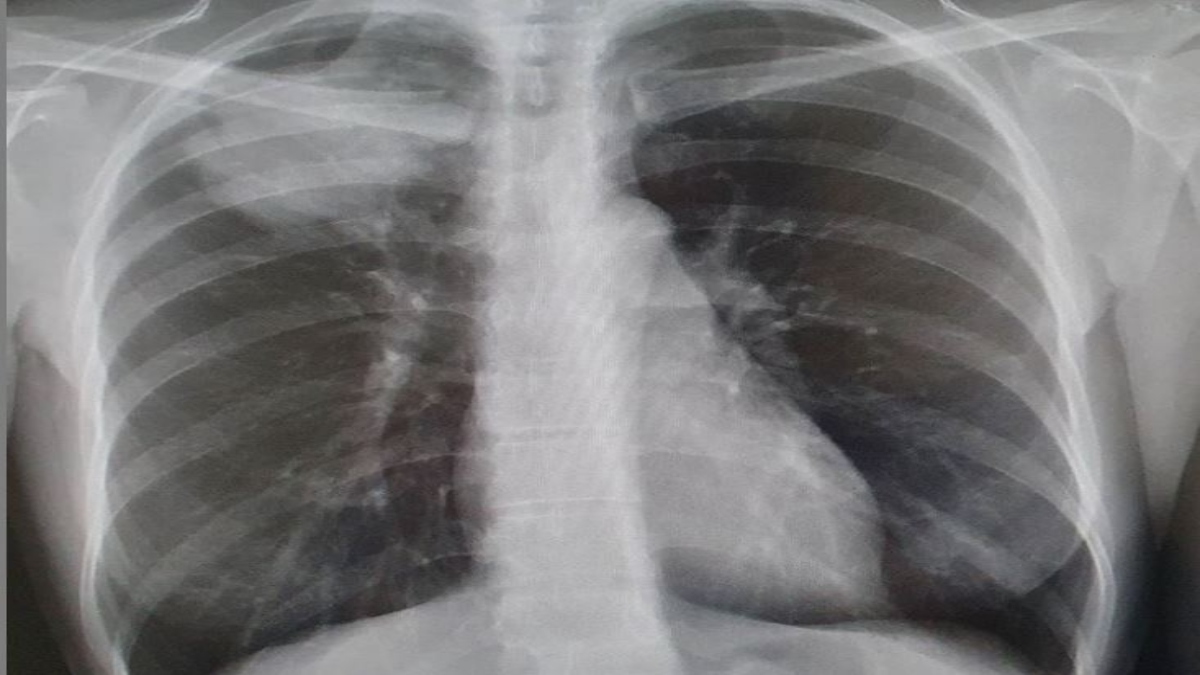

Idiopathic pulmonary fibrosis (IPF) is an acute lung disease distinguished by a progressive and irreversible reduction in lung functioning characterized by the thickening and damaging of air sac walls. This disease is characterized by the development of scar tissue within the lungs that begins at the edges and progresses toward the center, thus causing difficulties in breathing and insufficient delivery of oxygen to the body parts. Its symptoms include fatigue, nail clubbing, dry cough, weight loss, joint pain, and shortness of breath. It is diagnosed through lung biopsies, chest imaging studies, pulmonary function and antibody tests and can be treated using antifibrotic drugs, such as pirfenidone and nintedanib, and various other methods, including oxygen therapy, pulmonary rehabilitation, symptom management, and lung transplant.